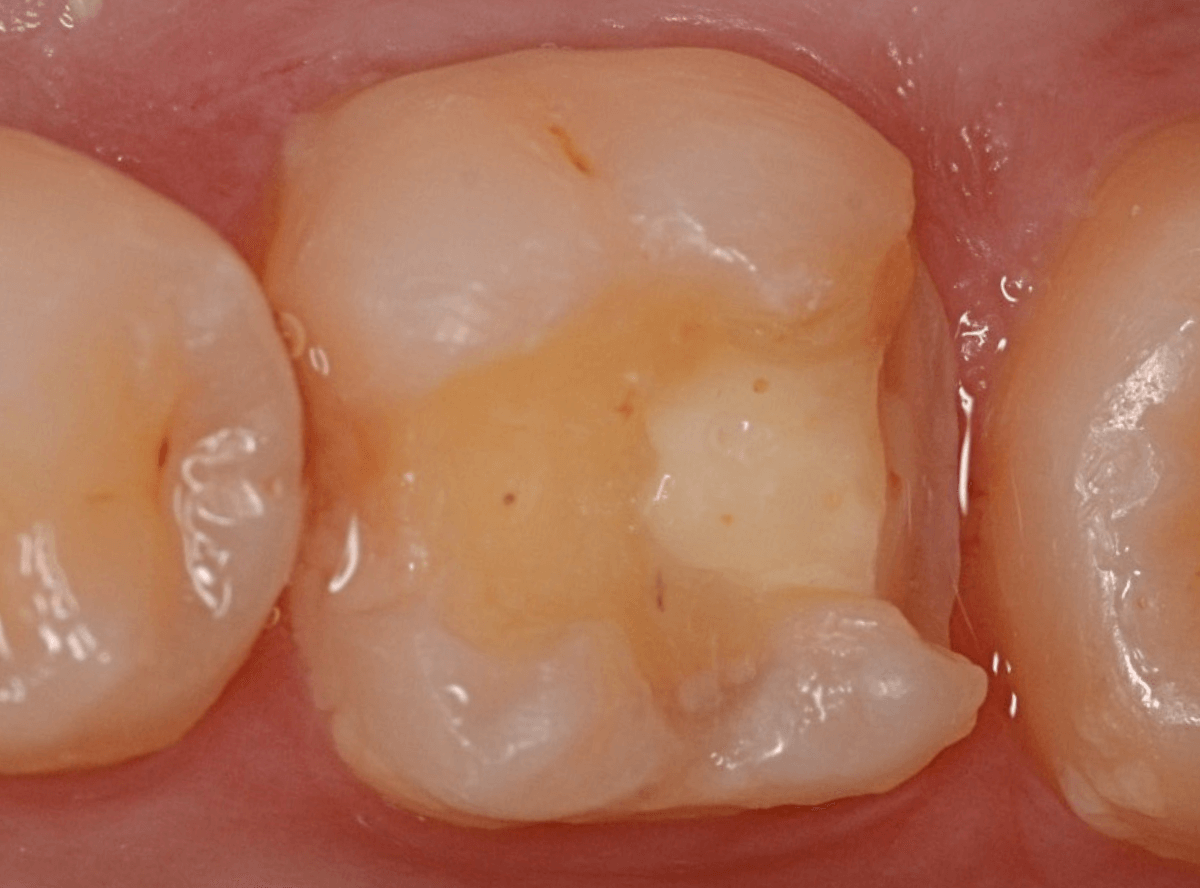

Case.28 虫歯治療後、半年以上来院されなかった患者さん

虫歯を治療して、セメントで歯を削った部分を封鎖した後、再修復を検討中で、半年以上来院されなかった患者さんです。

虫歯を治療して、セメントで封鎖した状態というのは、家でいえば、しっかりした屋根がない状態です。

今回は、セメントの一部がはがれる程度で済んでいましたが、虫歯が再発し、再治療、最終修復物の変更の可能性も出てきます。

治療再開後、セラミックの最終修復を希望されましたので、歯をトリミングし、型取りします。

治療後の状態です。

治療後の定期メンテナンスに来院されない患者さんもまれにいらっしゃいますが、一定期間来院のない方は破折などの際の保証も受けられません。

くれぐれも忘れずに来院していただくようにお話しし、終了となりました。

| 治療回数 | 3回 |

| 治療期間 | 3週間(中断期間は除く) |

| 費用 | ジルコニア・インレー (70,000円) +保険治療費用(虫歯除去など) |

(2024年10月)